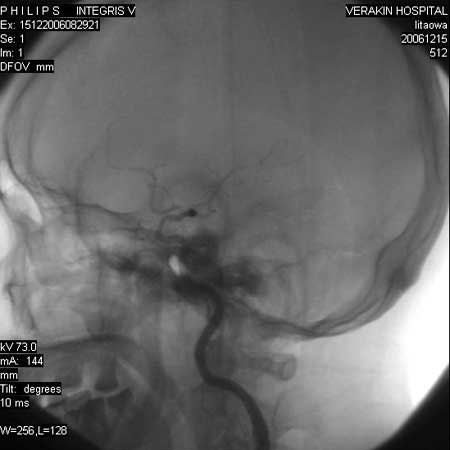

标题: DSA0063:颈内动脉血管造影

女,60岁,行全脑血管造影,图片较多,选了左颈内动脉造影100幅图中的10幅图片,请包涵。

实际上是左颈总动脉造影

更正:今天才看到本例脑血管造影全部过程,实际上仍是单侧的颈内动脉造影,只是在造影过程中,导管头位置平c4水平,刚好越过颈外动脉,本帖图片中颈外动脉显影系高压注射时造影剂部分返流到颈外动脉所致,特此更正!

另外:大家讨论的\"动脉瘤\"实际是血管分支重叠影像,本帖单侧颈内动脉仅见轻度动脉硬化性狭窄..参考旋转dsa请连接:http://www.sdhct.com.cn/radinet/read.php?tid=19818